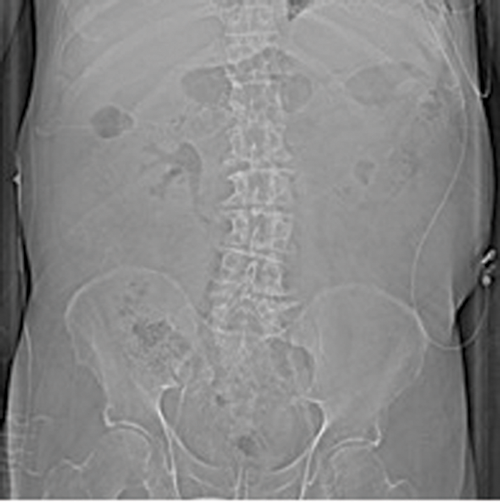

EPN should be suspected when a patient with multiple co-morbidities presents with severe sepsis and circulatory failure, combined with uncontrolled blood glucose. Other presenting symptoms include flank pain, pyrexia, vomiting, dysuria and pneumaturia. In some cases, crepitus in the flank and scrotum may be felt. Although gas may be seen on plain radiographs or ultrasound scan (USS), and ultrasound is a useful screening tool, the gold standard for imaging to determine the extent of the disease and plan intervention is a CT scan.